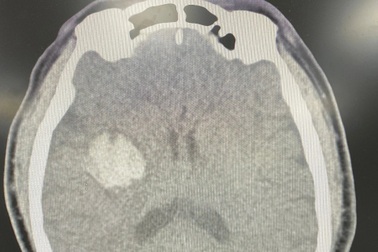

Uống An cung ngưu hoàng hoàn, nam bệnh nhân nhập viện cấp cứuKhi anh B.T.H. (50 tuổi) xuất hiện dấu hiệu đột ngột đau đầu, nôn vọt, khó nói, liệt nửa người, huyết áp tăng vọt liền được người nhà cho dùng loại thuốc An cung ngưu hoàng hoàn.